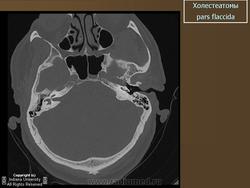

Диагностика холестеатомы представляет определенные трудности. Основными методами выявления холестеатомы последние несколько десятилетий остаются отоскопия (отомикроскопия) и рентгенологические методы (рентгенография в различных укладках и компьютерная томография). Компьютерная томография височных костей позволяет диагностировать холестеатому намного чаще, чем обычная рентгенография, однако степень достоверности данной диагностики остается невысокой, так как плотность холестеатомы практически соответствует плотности грануляционной ткани. Поэтому чувствительность метода КТ в диагностике холестеатомы составляет всего 71% при специфичности 55% [50]. Кроме того, следует учитывать, что указанный метод требует не только дорогостоящего оборудования, но и высококвалифицированных рентгенологов со специальной подготовкой, позволяющей им правильно интерпретировать полученные результаты.

2. Применение компьютерной томографии позволяет повысить степень обнаружения патологического процесса до 90% случаев, однако не позволяет достоверно дифференцировать холестеатому и грануляционную ткань по причине низкой специфичности метода (55%).

ID: 5467 Cholesteatoma - acquired Dr Frank Gaillard - 26 Jan 2009 CT through the temporal bone demonstrates a soft tissue mass in Prussak'...